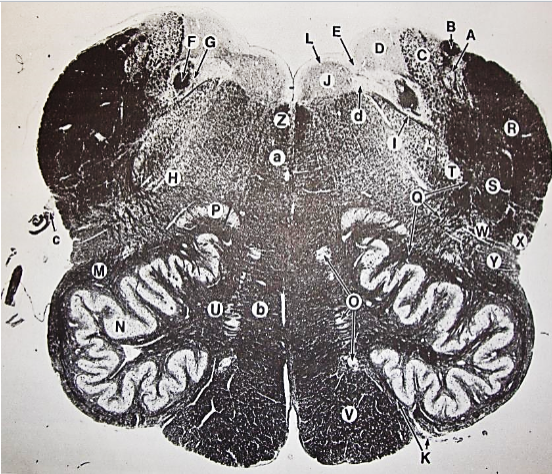

A

posterior median sulcus

B

posterior intermediate sulcus

C

anterior median fissure

D

gracile fasciculus

E

Gracile nucleus

F

fasciculus cuneatus

G

spinal trigeminal tract

H+I collectively

spinal trigeminal nucleus

J

Accessory nucleus

K

pyramidal decussation

L

lateral corticospinal tract

M

rubrospinal tract

N

posterior spinocerebellar tract

O

anterior spinocerebellar tract

P

lateral spinothalamic tract

Q

anterior spinothalamic tract

R

lateral vestibulospinal tract

S

medial longitudinal fasciculus

T

tectospinal tract

U

central canal